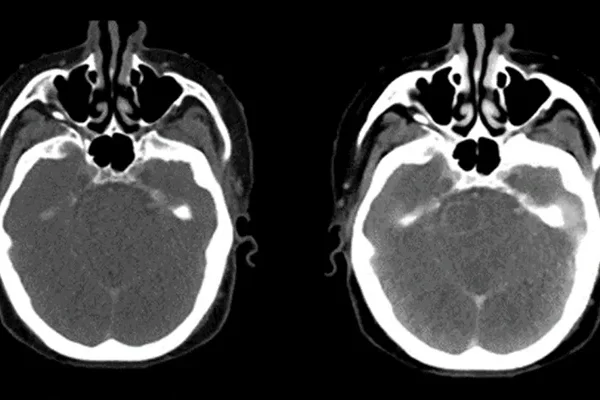

Radyoloji